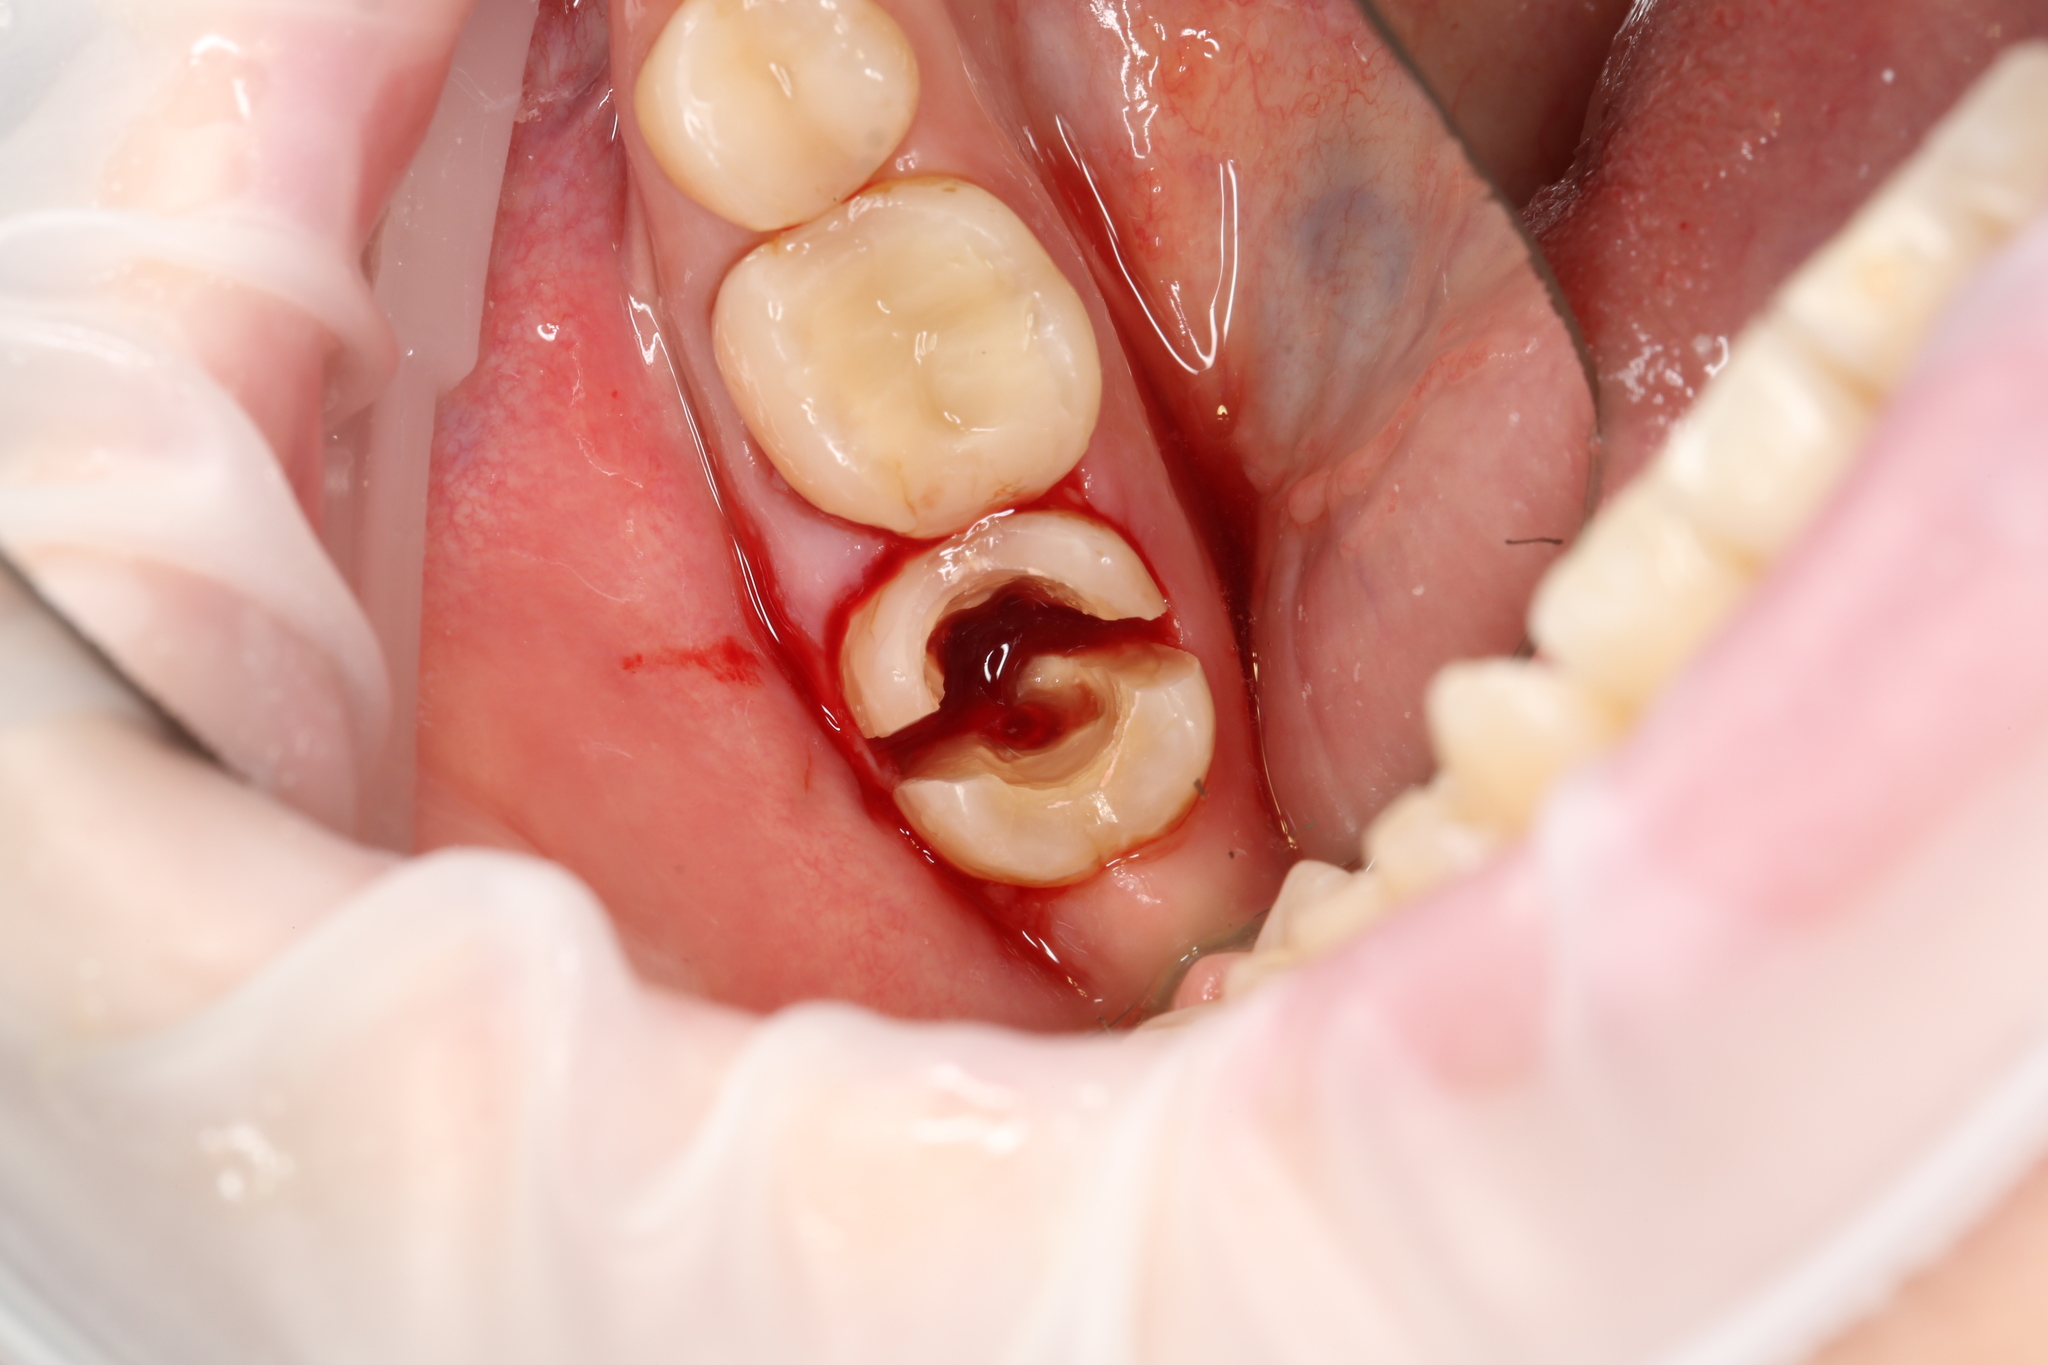

Небольшим бонусом пробегусь по удалению нижнего моляра. Они двухкорневые, но методика удаления схожа.

Был зуб (с временной пломбой):

Поделили его пополам:

И извлекли сначала один корень:

Затем второй:

Перегородка на месте, кровит хорошо: